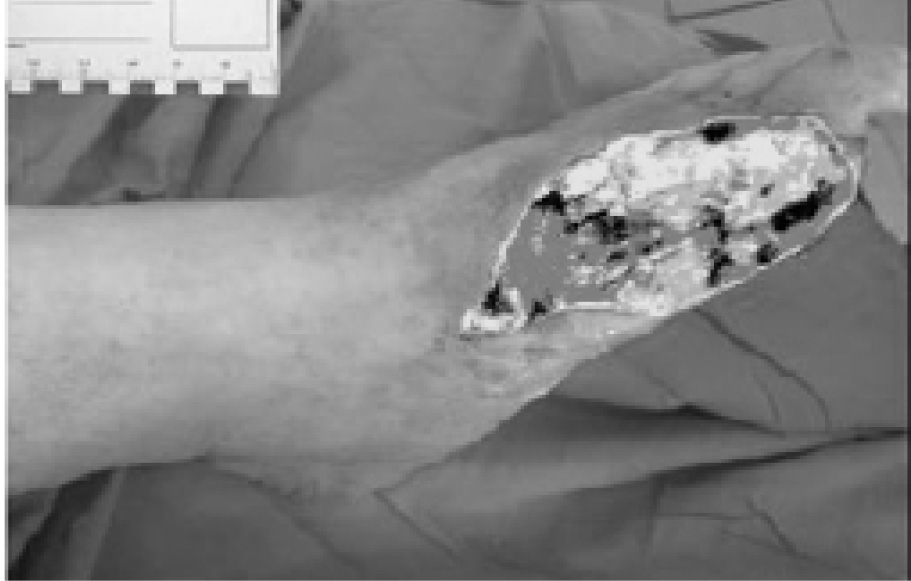

С целью объективизации скорости заживления раневого дефекта и расчета интегральных показателей применены методики цифровой фотографии и компьютерной планиметрии раны с использованием программы «Wound Analyzer» фирмы «Lohmann & Rauscher» (Австрия). Использовались цифровая камера (более 2 мегапикселей), фирменный осветительный прибор со световой температурой в диапазоне 4500–5000 К° для достижения безошибочного программного определения цветов на фотоснимке, Интернет (в настоящий момент существует лишь онлайн-версия программы) и оригинальная калибровочная линейка. Полученные фотографии загружались в онлайн-версию программы, где вручную выбирался центр калибровочного квадрата и обводилась зона раневого дефекта, после чего программа рассчитывала площадь раны и производили вычисление площади струпа, гноя, фибрина, грануляционной ткани и эпителия (рис. 2).

В качестве интегрального показателя оценивали скорость заживления раневого дефекта. Применены методики цифровой фотографии и компьютерной планиметрии с использованием программы «Wound Analyzer» фирмы «Lohmann & Rausher» (Австрия). После получения фотографии последние загружались в онлайн версию программы, в которой производился расчет площадей струпа, гноя, фибрина, грануляционной ткани и эпителия (основано на зарубежной цветовой классификации фаз раневого процесса «BYRP», разработанной JanieeZ.Cuzzell в 1988 г.). Уменьшение площади раны, выражаемое в процентах (ПУП), рассчитывали по формуле: ПУП = (S0 – S) × 100%/S0, где S0 — исходная площадь; S — площадь раны на момент измерения. Скорость заживления (СЗ) рассчитывали по формуле: СЗ = ПУП/Т, где ПУП — уменьшение площади раны в процентах; Т — количество дней между измерениями.

Из всех показателей компьютерной планиметрии ран (максимальные длина и ширина раны, площадь раны, абсолютные и относительные величины площади некроза, грануляций и эпителизации) наиболее информативными являются показатели площади некрозов и грануляций в ране, а также площадь раневого дефекта и скорость заживления раны.

По данным компьютерной планиметрии ран уменьшение площади раневого дефекта в 2 раза происходит за 37,1±4 дн. В период до 8 сут скорость заживления и процент уменьшения площади составляют в среднем 0,11±0,01%/сут и 0,12±0,1%/ сут соответственно. Относительная площадь некрозов в ране уменьшилась с 1-е по 8-е сут лечения с 57,9±7,1 до 8,9±1,3%, что составило в среднем 7%/сут. В период с 8-х по 11-е сут лечения относительная площадь некрозов ране уменьшилась с 8,9±1,3 до 0,8±0,5%, что составило в среднем 2,7%/сут.